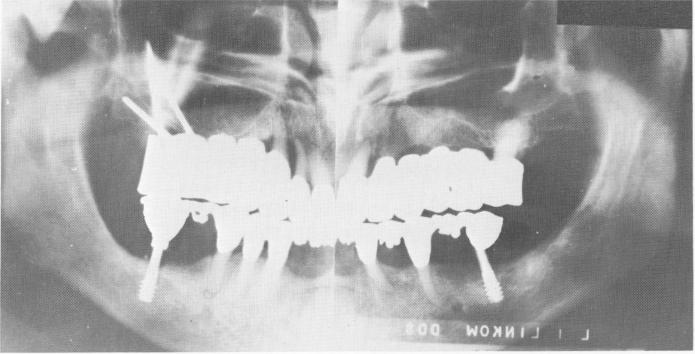

Fig. 15-83. A Panorex showing the pins extending into the zygomatic arch.

dible (Fig. 15-80) and the lower prosthesis cemented into position (Fig. 15-81). Final adjustments for proper articulation were accomplished in the mouth (Fig. 15-82) . A Panorex shows the case in the mouth (Fig. 15-83).

3 Panorex shows endosseous pin implants extending into zygomatic arch